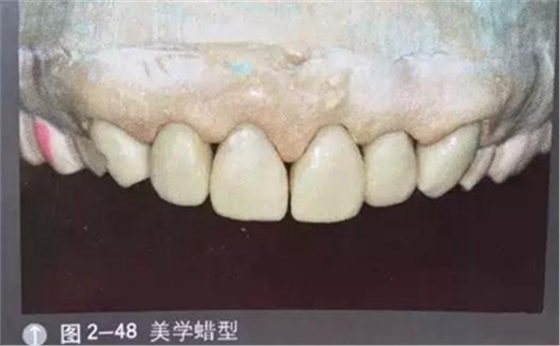

口腔攝影方法與技巧

診斷模型

診斷蠟型

工作模型